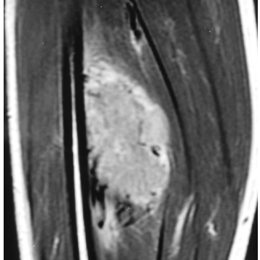

66B) Coronal T1 MRI Of Lower Leg Alveolar Soft Parts Sarcoma

Radiographic imaging is used to help form a diagnosis. These include MRI, CT and Bone Scans

An example of an MRI is shown.